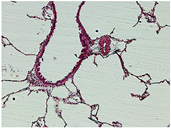

Table 2, Table 3, Table 4 and Table 5 present the results obtained through the multi-objective optimization image enhancement approach. Specifically, Table 2 and Table 3 show the results for natural images, while Table 4 and Table 5 display medical images. The tables are organized as follows: the first and second columns list the image names and their corresponding original, unenhanced versions. The third to fifth columns showcase the selected points from the Pareto front, representing the maximum contrast, knee point, and maximum detail, in that order. The final column illustrates the obtained Pareto front through the optimization process, with red, green, and orange points indicating the images that achieved maximum contrast, knee point, and maximum detail, respectively.

Table 5.

Medical image results—2.

As observed in the results, the images extracted from the Pareto front significantly maximize contrast and detail compared to the original images. In all study cases, the original image is dominated by the solutions extracted from the fronts, demonstrating the approach’s effectiveness in improving visual quality. However, the differences among the three enhanced images for each problem require a more detailed analysis.

For medical images, there are instances where differences are more perceptible. For example, in the Medical3 image, the maximum contrast solution makes it difficult to visualize the internal details of the basophil (a white blood cell highlighted in the box), which could result in a less accurate interpretation. In contrast, the knee and maximum detail solutions provide a clearer view of the interior of the white blood cell. Similarly, in the Medical5 image, the maximum contrast solution highlights the hand and arm bone structures. However, the maximum detail image offers a more precise view of the internal structures within the bones (see the highlighted region), which is crucial for a more detailed evaluation. Another notable example is the Medical8 image, where the maximum detail solution offers a more detailed view of the internal structure of the eosinophil (another type of white blood cell). However, the maximum contrast image improves the visibility of red blood cells. As shown in the yellow box, this solution reveals a red blood cell that is nearly imperceptible in the other solutions. An interesting case is the Medical6 image, where only a few non-dominated solutions are present on the Pareto front. Despite the similarities among the preferred solutions, the nodules are much more perceptible in the enhanced images than in the original image, as observed in the highlighted region.